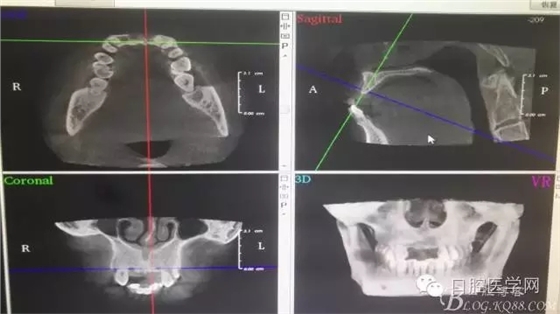

為他院轉(zhuǎn)診患者。男,無(wú)吸煙史,前牙因齲壞治療后,外力折斷導(dǎo)致拔除?,F(xiàn)拔除該牙后兩個(gè)多月。 左上區(qū)域骨寬度不足,計(jì)劃植入種植體同期GBR。

左上區(qū)域骨寬度不足,計(jì)劃植入種植體同期GBR。